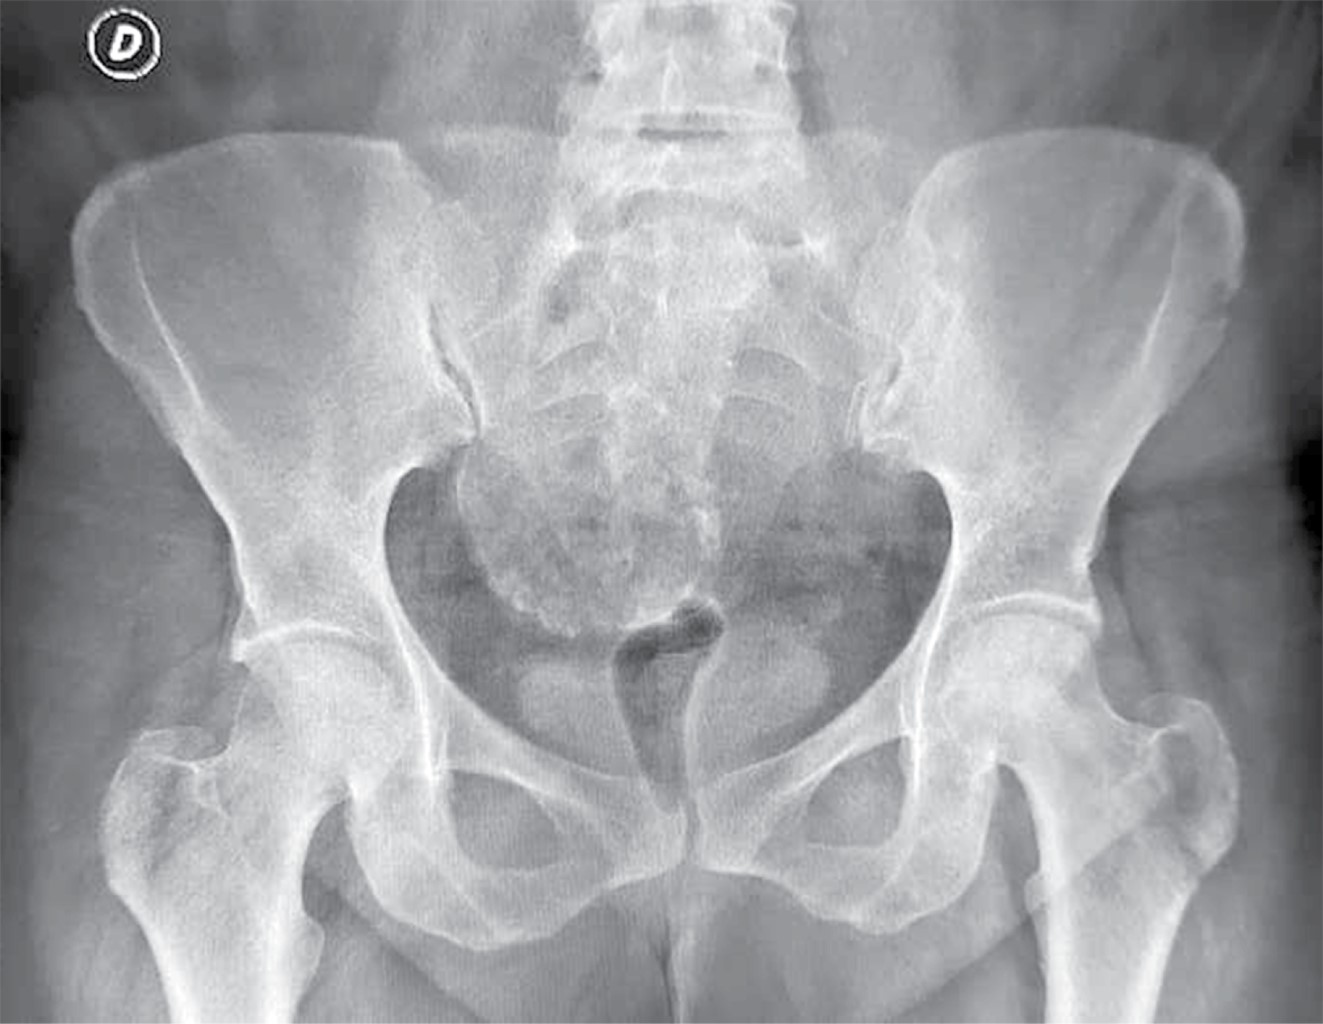

Todos los pacientes habían recibido corticosteroides como parte de su régimen de tratamiento para COVID-19 con dosis promedio de 480 mg, en un rango de 400 a 1,200 mg de hidrocortisona (o su equivalente –se adjunta tabla de conversión–) (Tabla 1). Estos pacientes mostraron síntomas clásicos de NAVCF caracterizados por un rápido deterioro funcional con sintomatología clínica de dolor, limitación a la carga y movilización. Asimismo, presentaron los cambios correspondientes en las imágenes de radiografías y resonancia magnética nuclear (RMN); los estadios de necrosis fueron clasificados según Ficat8 (Figuras 1 y 2). Se incluyeron estadios I a III de la clasificación dada la juventud de la serie y que no tenían artrosis con disminución del espacio articular.

Con base en la evaluación radiografía y de resonancia magnética nuclear, los pacientes fueron organizados de acuerdo con la clasificación de Ficat: estadio I, 10 (47.6%) casos; estadio II, seis (28.6%) casos y estadio III, cinco (23.8%) casos (Tabla 2).